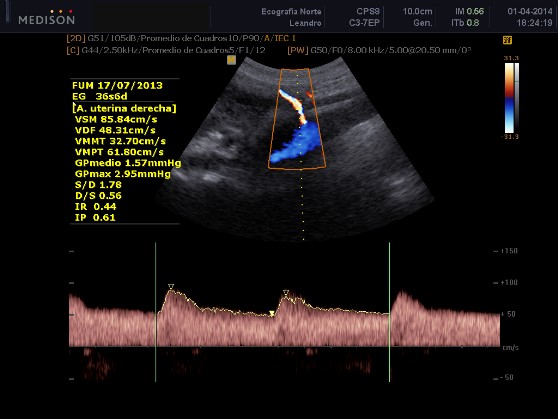

También por medio del estudio de la circulación materna (arterias uterinas) sirve para evaluar el riesgo de padecer enfermedades hipertensivas durante el embarazo.